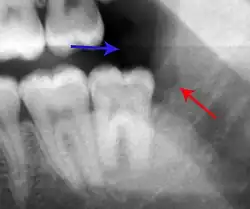

Lateral periodontal abscess (blue arrows) due to a fracture (green arrows)

A periodontal abscess (lateral abscess) is a collection of pus that forms in the gingival crevices, usually as a result of chronic periodontitis where the pockets are pathologically deepened greater than 3mm. A healthy gingival pocket will contain bacteria and some calculus kept in check by the immune system. As the pocket deepens, the balance is disrupted, and an acute inflammatory response results, forming pus. The debris and swelling then disrupt the normal flow of fluids into and out of the pocket, rapidly accelerating the inflammatory cycle. Larger pockets also have a greater likelihood of collecting food debris, creating additional sources of infection.[21]: 443

Periodontal abscesses are less common than apical abscesses, but are still frequent. The key difference between the two is that the pulp of the tooth tends to be alive, and will respond normally to pulp tests. However, an untreated periodontal abscess may still cause the pulp to die if it reaches the tooth apex in a periodontic-endodontic lesion. A periodontal abscess can occur as the result of tooth fracture, food packing into a periodontal pocket (with poorly shaped fillings), calculus build-up, and lowered immune responses (such as in diabetes). Periodontal abscess can also occur after periodontal scaling, which causes the gums to tighten around the teeth and trap debris in the pocket.[21]: 444–445  Toothache caused by a periodontal abscess is generally deep and throbbing. The oral mucosa covering an early periodontal abscess appears erythematous (red), swollen, shiny, and painful to touch.[22]